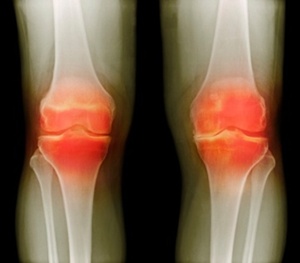

금천구에 위치한 관절전문 희명병원(이사장 최백희) 정형외과 전문의 김정민 진료부장은 “퇴행성 관절염은 뼈와 뼈 사이에서 완충 역할을 해주던 연골, 일명 물렁뼈가 손상 되거나 퇴행성 변화로 인해 관절을 이루는 뼈와 인대 등에 염증이 생기는 질환을 말합니다. 대개는 많이 사용 되는 무릎관절과 고관절, 척추관절, 손가락 관절 등에 퇴행성 관절염이 찾아오죠”라며 퇴행성관절염의 발병하는 부위에 대해 설명했다.

퇴행성 관절염은 심한 통증과 함께 시간이 지날수록 점점 일상생활에 지장을 초래하게 된다. 퇴행성 무릎관절염의 경우 다리가 O자 형태로 휘게 되며 정상적인 보행이 불가능해지며 손가락에 관절염이 찾아올 경우 젓가락질 조차 힘들어지게 된다.